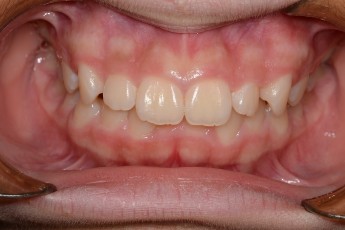

Before

After

- 덧니교정